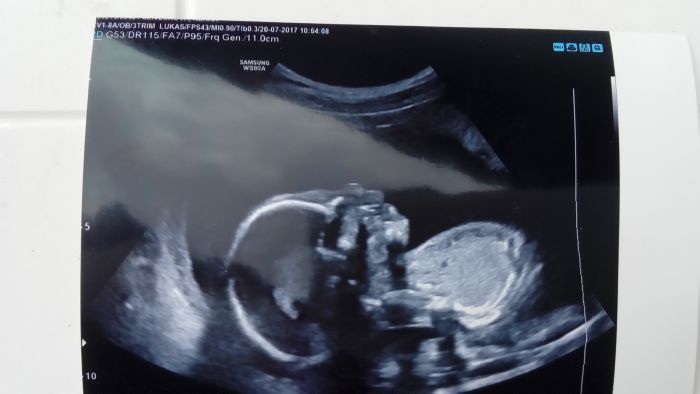

Klarus mas krásný roztomilý brisko...

moc ti tehu sluší...opatruj se. Mimisek je krasnej!